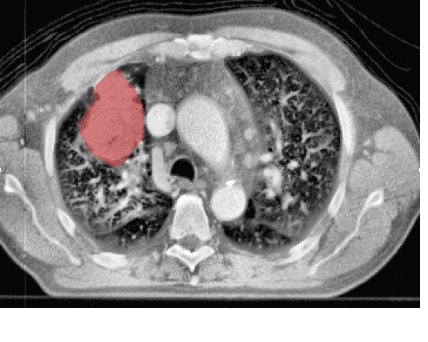

Abstract:Identifying image features that are robust with respect to segmentation variability and domain shift is a tough challenge in radiomics. So far, this problem has mainly been tackled in test-retest analyses. In this work we analyze radiomics feature stability based on probabilistic automated segmentation hypotheses. Based on a public lung cancer dataset, we generate an arbitrary number of plausible segmentations using a Probabilistic U-Net. From these segmentations, we extract a high number of plausible feature vectors for each lung tumor and analyze feature variance with respect to the segmentations. Our results suggest that there are groups of radiomic features that are more (e.g. statistics features) and less (e.g. gray-level size zone matrix features) robust against segmentation variability. Finally, we demonstrate that segmentation variance impacts the performance of a prognostic lung cancer survival model and propose a new and potentially more robust radiomics feature selection workflow.